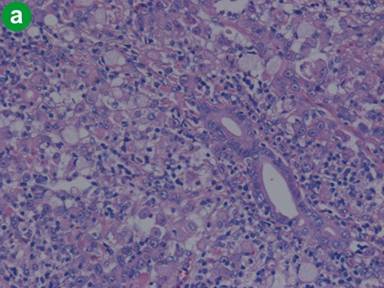

Macroscopically, the tumor measured 1.5x1.5x2 cm and the tumor surface was exposed at the papilla, showing that its surface was nodular, but there was no ulceration. Histologically, signet-ring cell carcinoma was predominant, but partially well- to poorly-differentiated tubular adenocarcinoma also existed in the lesion (Figure 3a). Signet-ring cell carcinoma arose from the ampulla of Vater, slightly involving the muscularis propria of the duodenum and infiltrating the pancreatic parenchyma. The cytoplasm of the signet-ring cell carcinoma was positive for periodic acid Schiff staining (Figure 3b). Lymphatic and vascular involvement was seen in parts, but resected lymph nodes were free from metastasis. Immunohistochemical staining was performed and both the signet-ring cells and the adenocarcinoma cells were positive for human gastric mucin (45M1) (Figure 4). Both types of tumor cells were positive for CK7, MUC1 and MUC6, but negative for CK20, MUC2 and CD10 (Figure 5). The signet-ring cell carcinoma was partially positive for CDX2 (Figure 6). The carcinoma of the ampulla of Vater was diagnosed as T3N0M0 stage IIA according to the International Union Against Cancer TNM classification. The patient did not receive chemotherapy. Six months after surgery, the patient developed pneumonia. Subsequently, the pneumonia worsened and the diabetes mellitus also deteriorated. The patient finally died from multiple organ failure due to sepsis. However, no recurrence of the signet-ring cell carcinoma was detected on repeated imaging studies.

Figure 4. Immunohistochemical findings for human gastric mucin (45M1). Signet-ring cells and adenocarcinoma cells were both positively stained. (original magnification x100). |